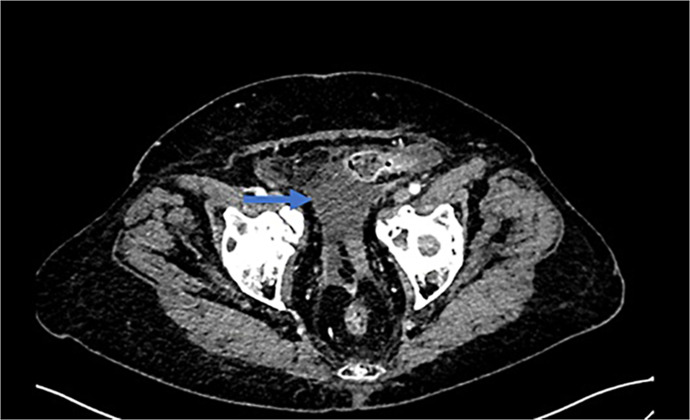

Case presentation: Although VPF mainly occurs as an early postoperative complication of gynecological surgery, we report a case of a 71-year-old female patient who presented with ascites, pseudo-renal failure, and peritonitis caused by a VPF as a delayed complication of radiotherapy.

Conclusion: In this case report, we discuss treatment strategies based on previously published case studies and our experience. We provide a diagnostic overview of commonly available imaging techniques, such as computed tomography scans and magnetic resonance imagings. Despite their widespread use, these imaging modalities have not led to any shift in the diagnostic process, with the definitive diagnosis being confirmed only by retrograde cystography.